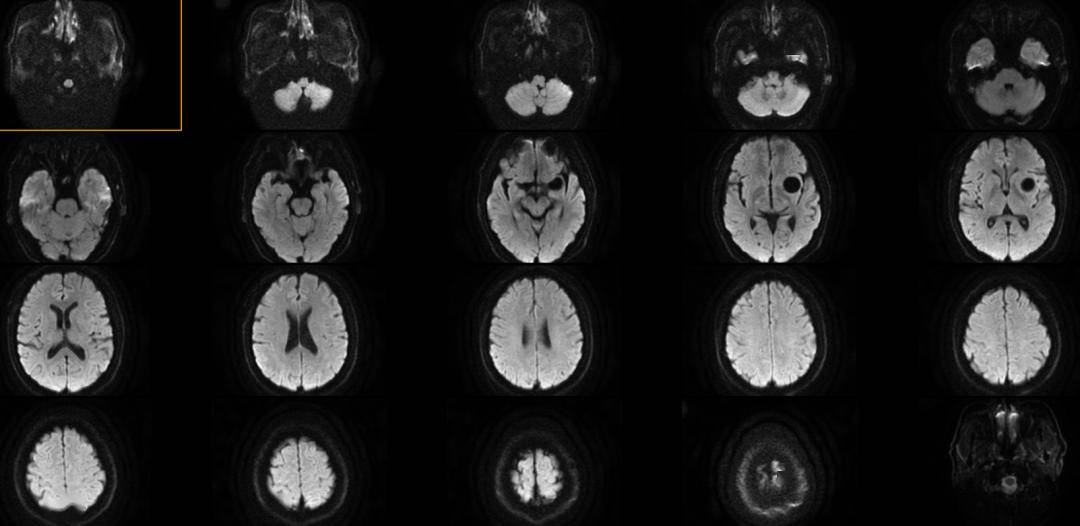

支架特性优势:Lattice自带的机械球囊设计,分段吸收张力,使支架能逐步贴合血管壁;释放过程中头端导丝稳定不前移,保护分支血管安全,在M1段这种短而复杂的血管里表现尤为突出。

操作体验:先释放Lattice 并确认贴壁满意,再在瘤腔内置入弹簧圈。借助支架的屏障作用,弹簧圈堆积稳定,不存在突出或滑脱问题。

即刻疗效:造影显示瘤腔完全闭塞,瘤颈覆盖理想,邻近分支血流通畅。